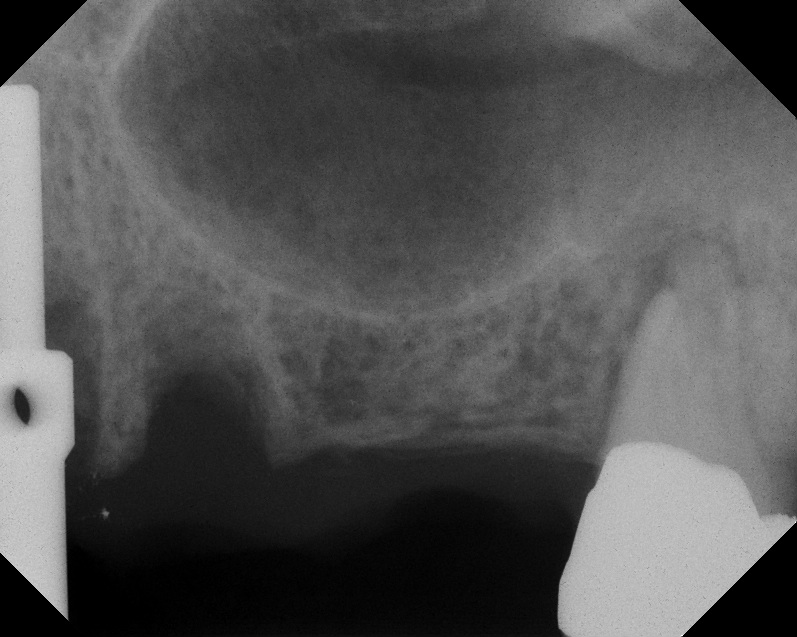

Case 1. Preoperative radiograph showing a ridge height of about 2 mm to 3 mm in the No. 14 position.

Fig. 13